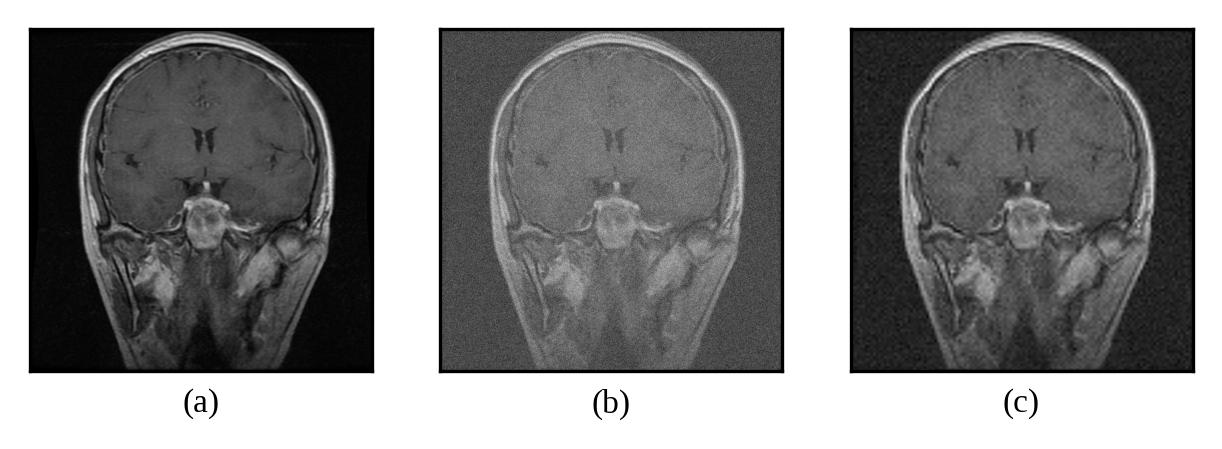

Representative denoising results are illustrated in Figures 2 through 7, demonstrating the visual improvement achieved by both thresholding methods across different noise levels.

Figure 3: (a) Original Image, (b) Noisy Image(μ=0\mu=0, σ=10\sigma=10), (c) Denoised Image (with threshold value τuniversal\tau_{universal})

Refer to caption